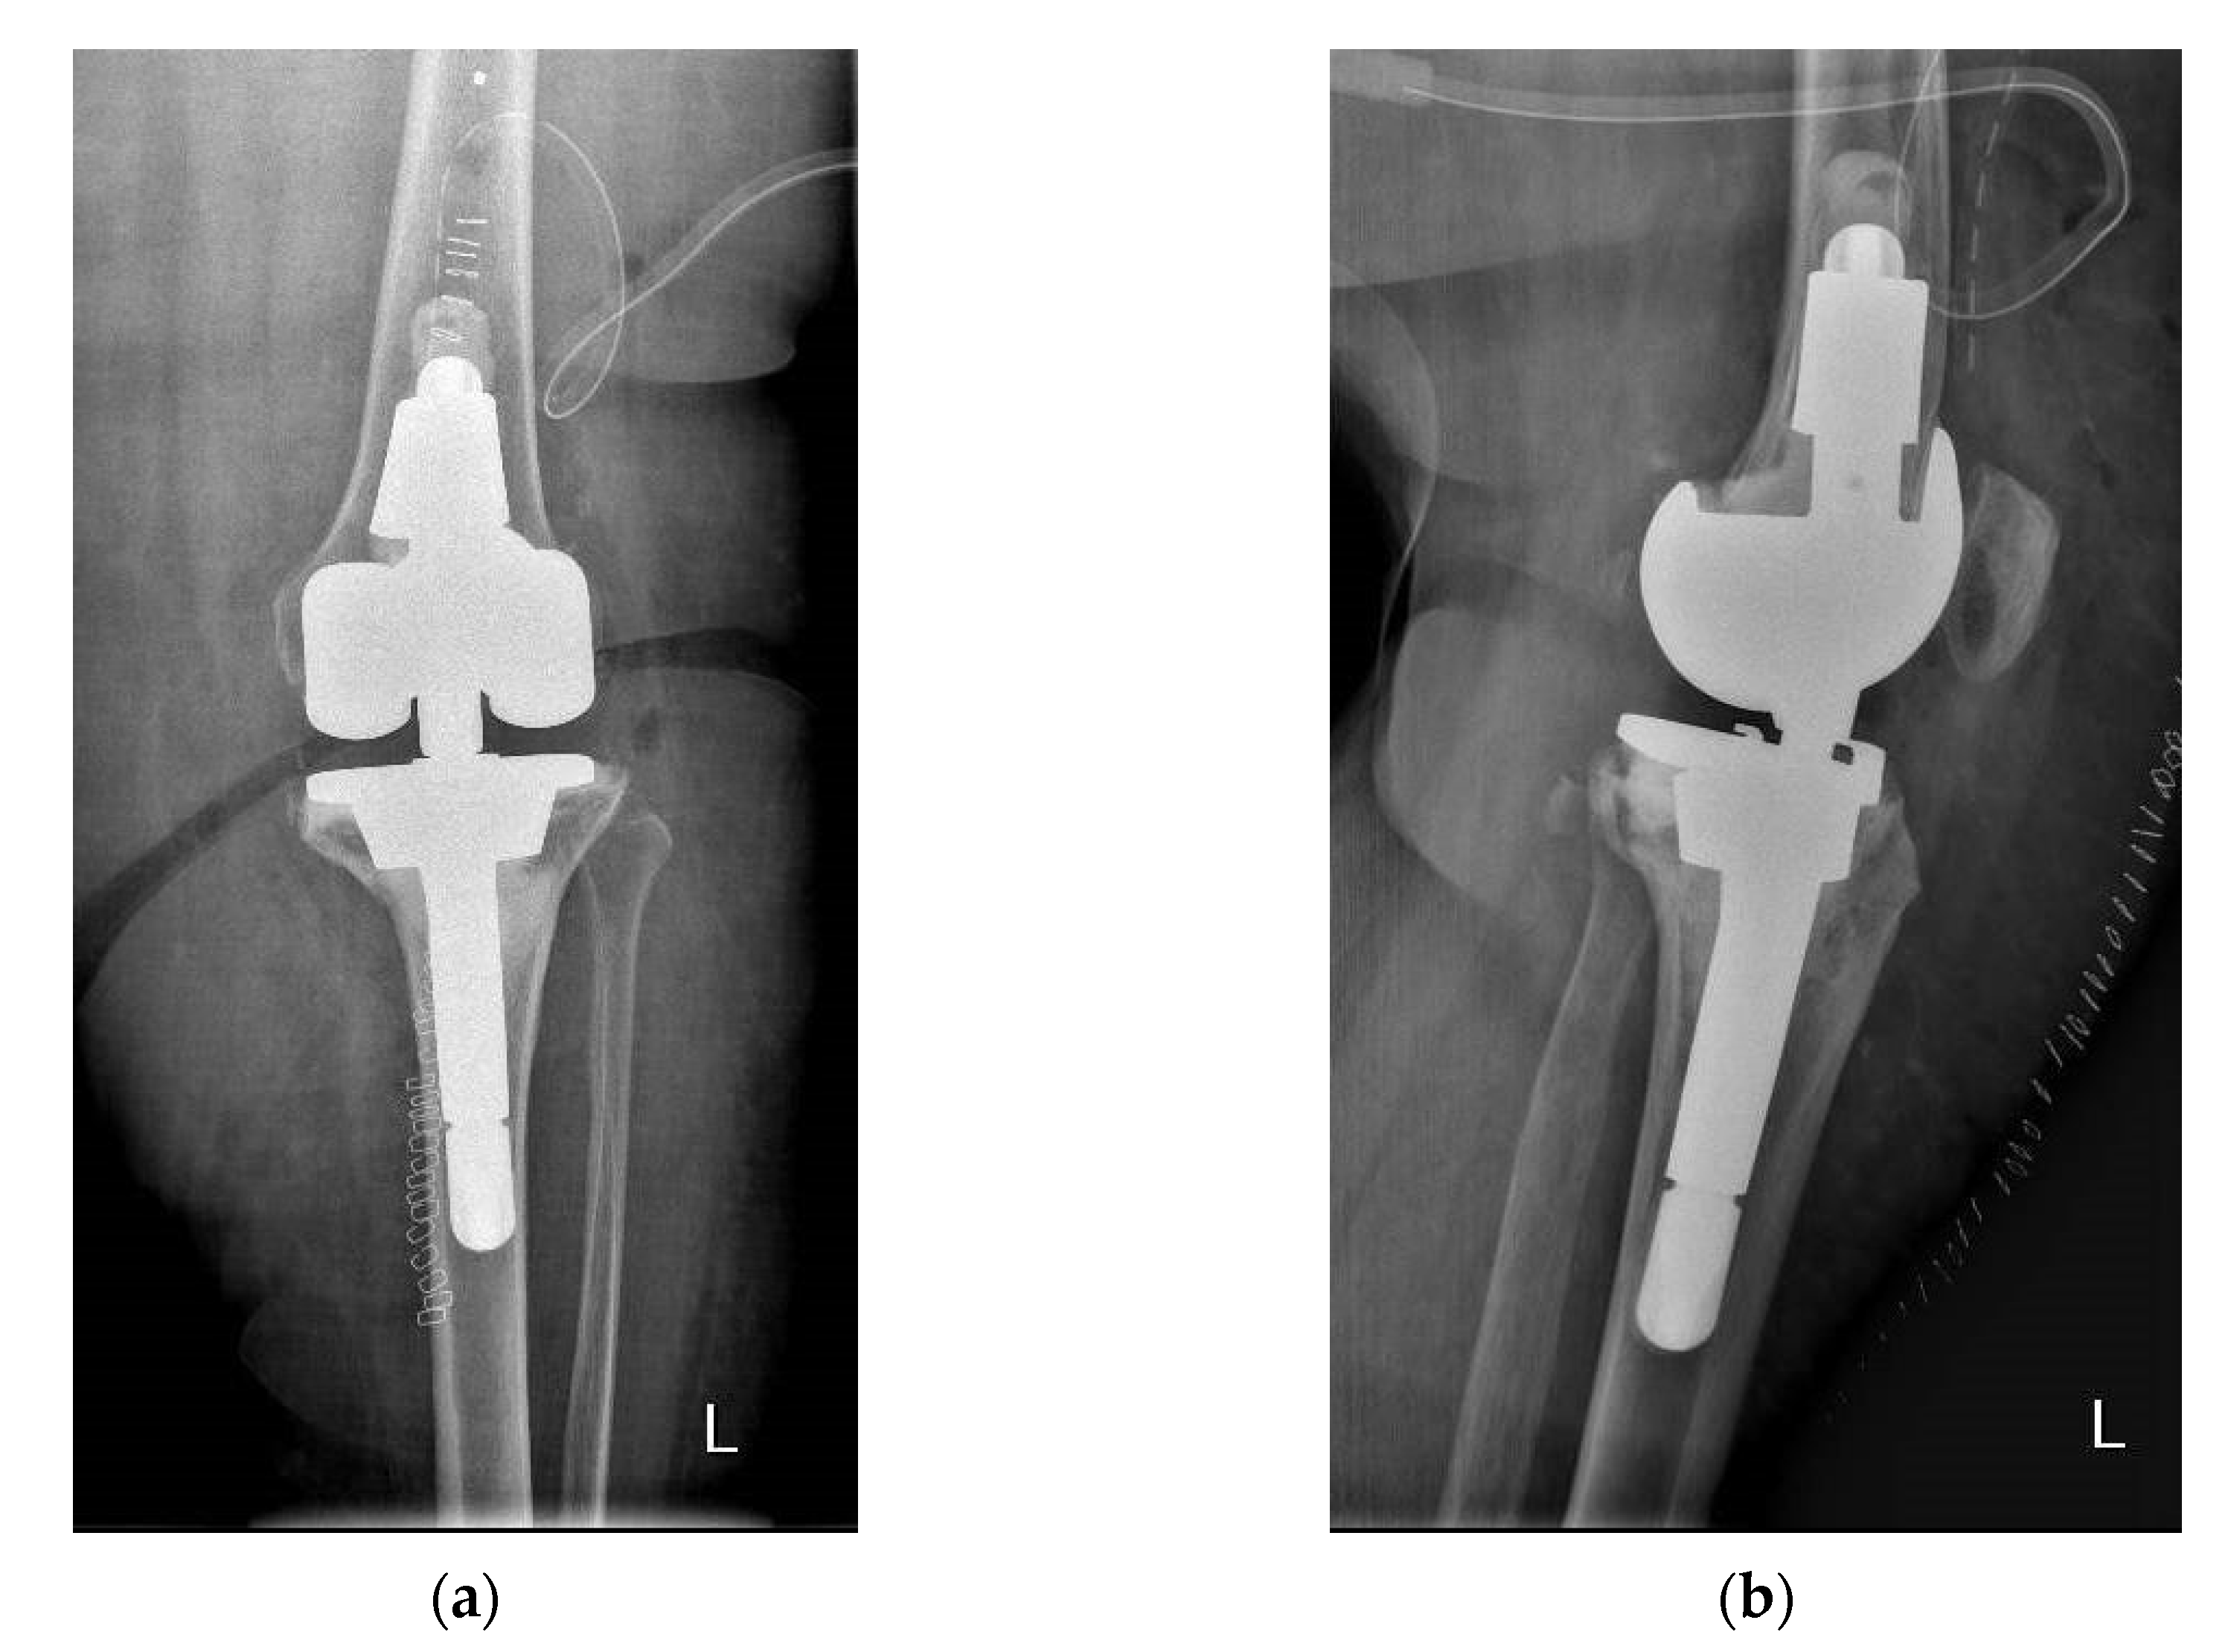

Figure 2 from Hinge total knee replacement revisited. Semantic Scholar

Figure 2 from Hinge total knee replacement revisited. Semantic Scholar Constrained Hinged Knee Replacement Gunston introduces first cemented surface arthroplasty of knee joint 1970 guepar develops a new hinged prosthesis based on design by walldius that increases motion. To address instability in primary tka, implants with varying degrees of constraint are available. There is debate in the literature whether rotating hinge knee (rhk) or. Tibiofemoral instability is increasingly recognized as a common mode of. Constrained Hinged Knee Replacement.